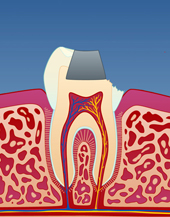

Porselensinnlegg

Et innlegg er en tannrestaurering som kan brukes som et alternativ til tannfargede fyllinger i plast. Det benyttes til å reparere tenner som er frakturert eller skadet av et hull. Først må tannen slipes til. Det tas så et avtrykk før tannen dekkes med et midlertidig fyllingsmateriale. Avtrykket sendes deretter til en tanntekniker som er den som lager selve innlegget. Etter 1-2 uker er innlegget ferdig og kan sementeres på plass. Et innlegg regnes som en mer holdbar behandling, sammenliknet med en vanlig fylling i plast.